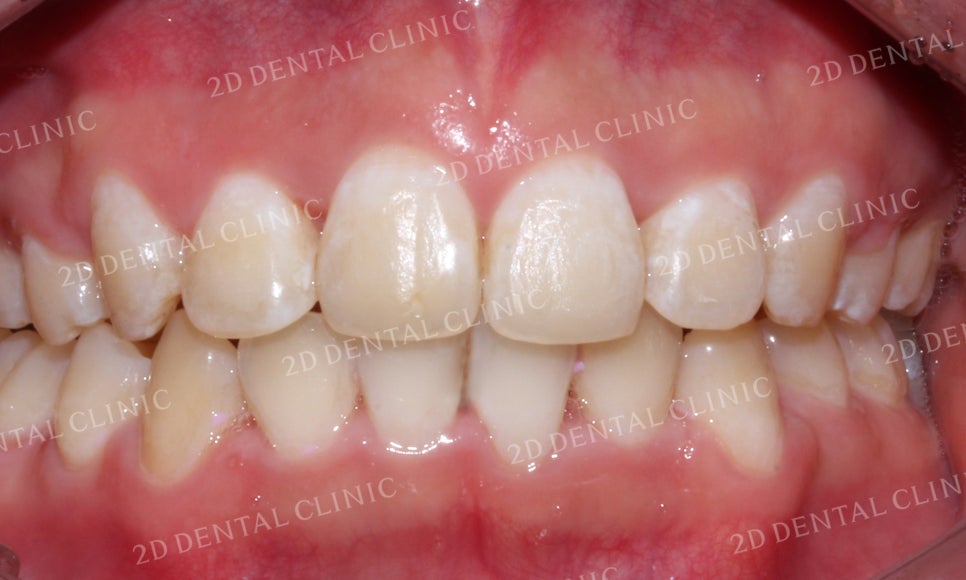

미소 시 전치부의 모습을 보시면

교정 전 전치부의 크라우딩으로 인해

심하게 삐뚤거리던 치아들이

교정 후 가지런하게 배열된 모습입니다.

돌출앞니 전체교정 후